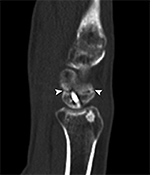

Fracture healing and joint fusion may be assessed readily with radiographs, but the presence of callus formation alone does not predict progression to complete healing, and the presence of osseous bridging is considered a more reliable indicator of union (Figure 9) (Ohashi, 2009). CT has been found to be more accurate for the determination of osseous bridging, as radiographs may either underestimate or overestimate the extent of bone fusion (Krestan, 2006; Grigoryan, 2003). The presence of exuberant callus formation may obscure the evaluation for osseous bridging on radiographs, and multiplanar CT allows direct visualization of the fracture site. In addition, fine central osseous bridging at the site of small fractures and bone grafts, such as in treated, non-united scaphoid fractures, is better assessed with thin slice CT images (Figure 10). Finally, some articulations are difficult to assess due to overlapping anatomy, such as the posterior subtalar and Lisfranc joints, and CT offers superior delineation of the joint spaces following arthrodesis.

Scaphoid Fracture Evaluation. (A) Sagittal multiplanar reformation shows central portion of compression screw in the scaphoid with incomplete union at periphery of fracture site (arrowheads). Note absence of streak artifact due to small size of screw. (B) Coronal multiplanar reformation shows fracture union at the central portion of the scaphoid waist, indicating partial union.